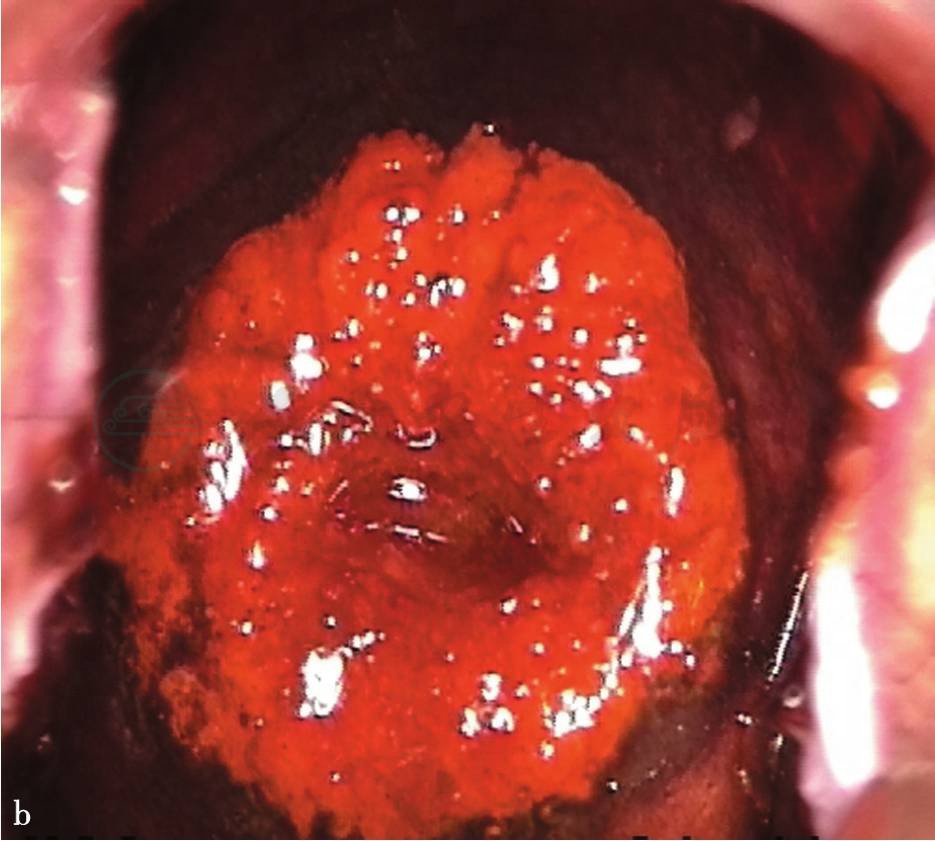

碘试验的主要原理:碘试验主要是利用碘对糖原的敏感,用碘液后含有糖原的上皮可吸收碘,原始的和新形成的成熟鳞状化生上皮含有糖原,而CIN和宫颈浸润癌几乎不含或没有糖原、柱状上皮不含糖原,未成熟的化生鳞状上皮通常没有或偶有糖原。含糖原的鳞状上皮涂碘液后可染成棕褐色或黑色;柱状上皮不染色,但因有一薄层碘液,看起来略有染色;而未成熟的化生鳞状上皮区不染色或仅部分染色;因炎症导致鳞状上皮缺失或“糜烂”,涂碘后不着色或在黑色或褐色背景周围还有一些独特的无色区;CIN和宫颈浸润癌部位不吸碘,呈现深的芥末黄或红褐色区;白斑不着色;湿疣不着色或偶尔仅部分着色(图1)。

图1 碘试验

a.肉眼观察(VILI)阳性;b.肉眼观察(VILI)阴性